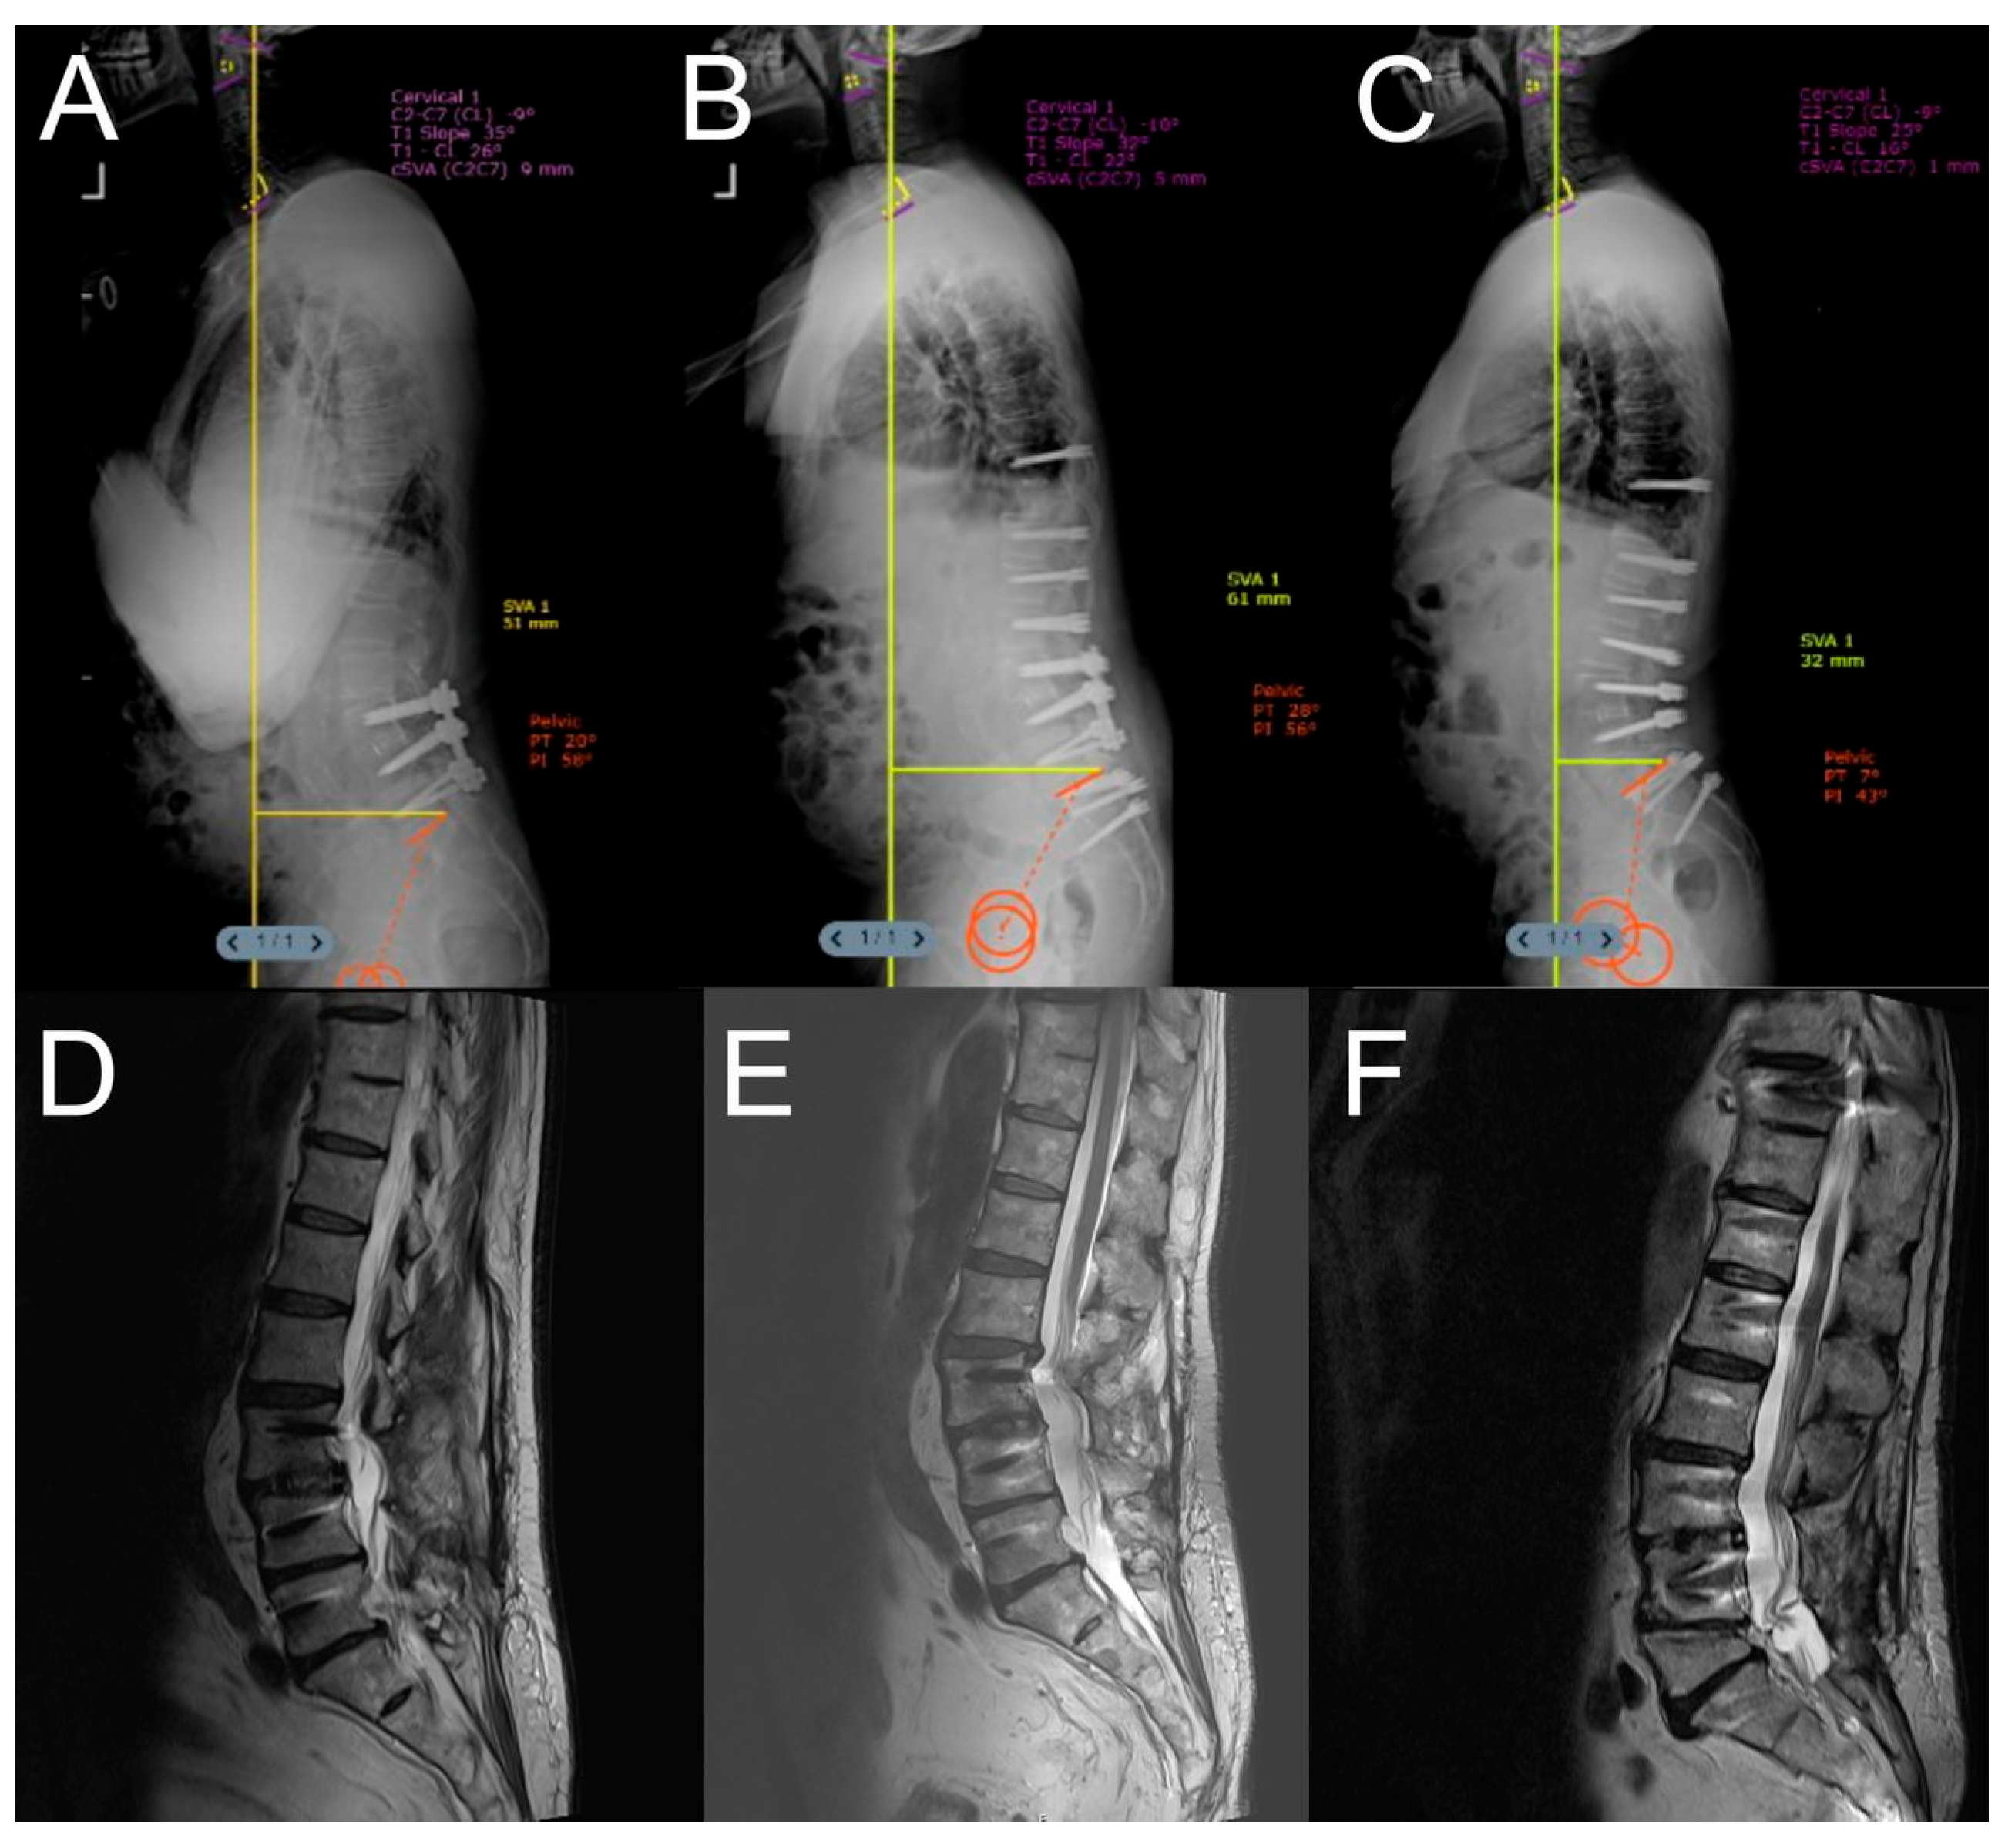

- Ozer, A.F.; Akgun, M.Y.; Ucar, E.A.; Hekimoglu, M.; Basak, A.T.; Gunerbuyuk, C.; Toklu, S.; Oktenoglu, T.; Sasani, M.; Akgul, T.; et al. Can Dynamic Spinal Stabilization Be an Alternative to Fusion Surgery in Adult Spinal Deformity Cases? Int. J. Spine Surg. 2024, 18, 152–163. [Google Scholar] [CrossRef] [PubMed]